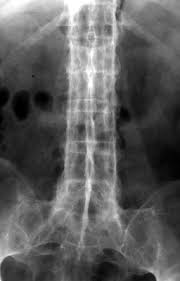

X-ray shows holly leaf appearence in _____.